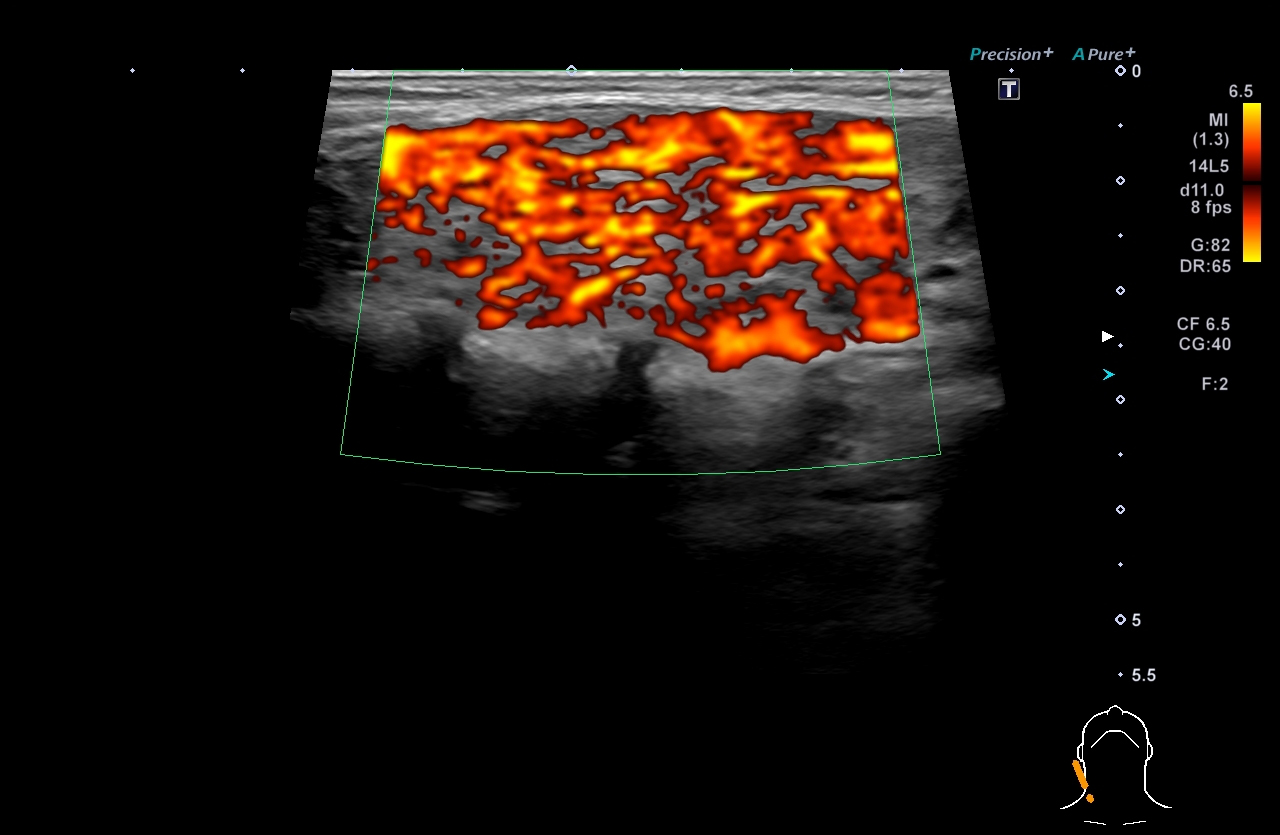

超音波(エコー)

下記など多くの診断ができます。

各項目をクリックすると診断画像が表示されます

超音波(エコー) 診断画像

- 内頸動脈狭窄

- 膀胱がん

- 粉瘤

- 膝窩靭帯炎

- 乳腺症

- 乳がん

- 転移性肝がん

- 胆嚢ポリープ

- 胆石

- 大腸がん

- 前立腺肥大・前立腺がん

- 静脈瘤

- 腎細胞がん

- 子宮筋腫

- 心エコー(大動脈弁・僧帽弁閉鎖不全症)

- 鎖骨上転移

- 頸部リンパ節転移

- 胃がん

- バセドウ病